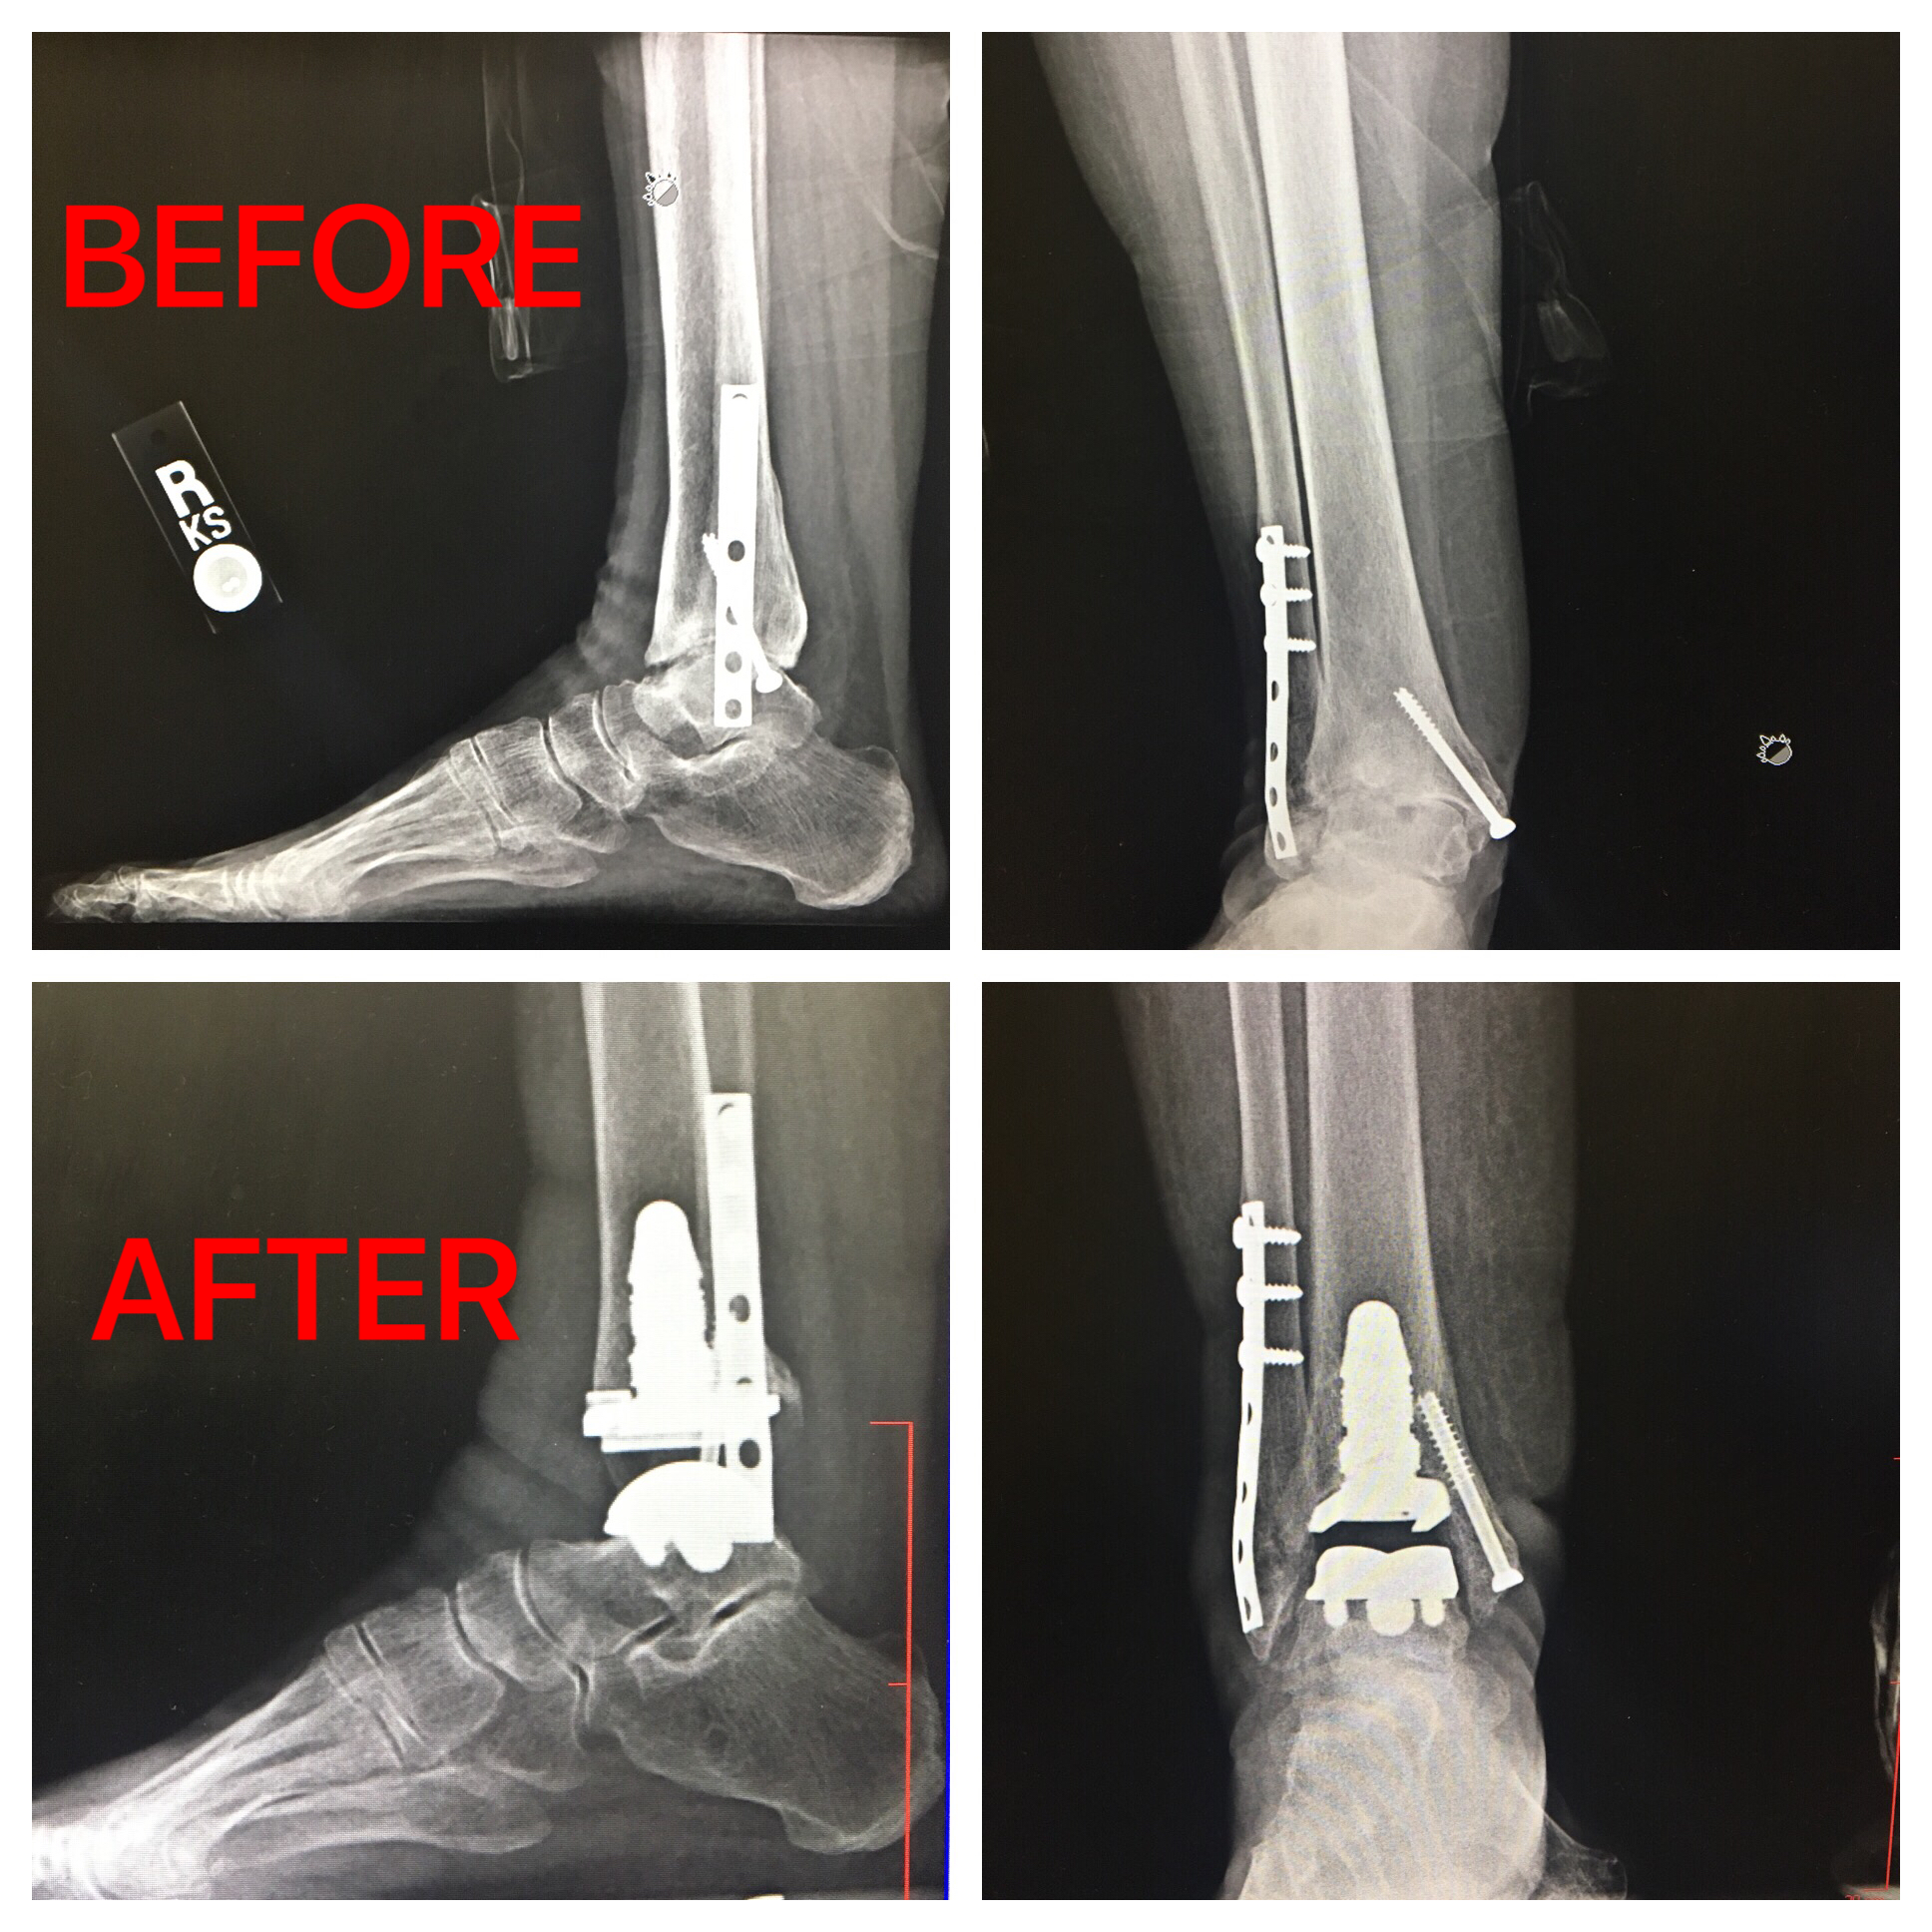

Total Ankle Replacement Surgery - Stock Image - C041/2282 - Science

www.sciencephoto.comTotal Ankle Replacement Before & After | The Orthopaedic Group, P.C.

www.sciencephoto.comTotal Ankle Replacement Before & After | The Orthopaedic Group, P.C.

www.theorthogroup.comankle replacement total after before success patient story

www.theorthogroup.comankle replacement total after before success patient story